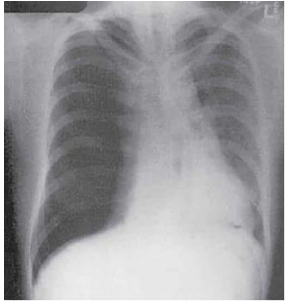

Paciente de 30 anos, masculino, tabagista e usuário de maconha,

deu entrada no Posto de Saúde com quadro de dor torácica de

início súbito (sem história de trauma recente), dispneia,

taquipneia, PA 100x70 mmHg, FC 110 bpm com ritmo sinusal.

Realizada radiografia de tórax, representada na imagem abaixo.